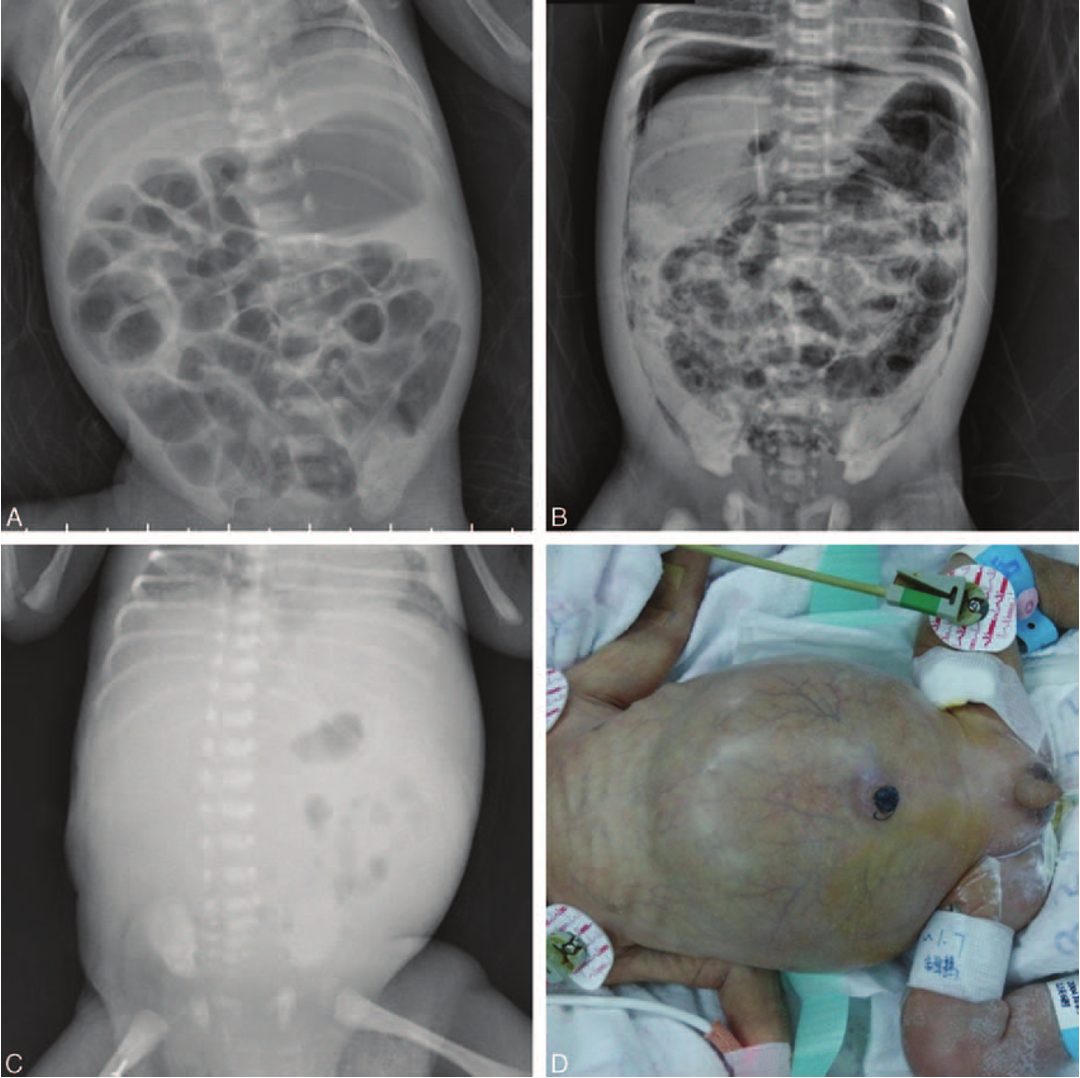

Radiography: Abdominal X-ray:

- Dilated loops,

- thickened bowel walls,

- pneumatosis intestinalis (air in intestinal walls),

- pneumoperitoneum; indicate perforation (emergency requiring surgical intervention),

- portal gas (present in the portal venous system,

- considered to be a poor prognostic sign).

3rd abnormal gas patterns

4th cellulitis/perforation

3rd abnormal gas patterns

4th cellulitis/perforation

- Cellulitis of the abdominal wall